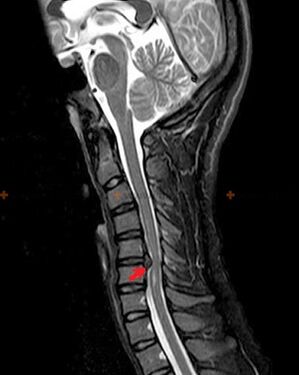

Diagnostics et signes radiologiques

L'ostéochondrose est un diagnostic radiologique, car un tableau clinique détaillé n'est présent qu'au moment de l'exacerbation, tandis que lorsqu'une personne est en parfait bien-être subjectif, des modifications de la colonne vertébrale peuvent survenir. Sans examen radiologique, on ne peut parler que d'une suspicion d'ostéochondrose, car des symptômes similaires peuvent également être provoqués par d'autres maladies (myosite, néoplasie vertébrale, etc.).

Pour diagnostiquer l'ostéochondrose, les méthodes d'examen suivantes sont utilisées : radiographie (de préférence avec tests fonctionnels), MSCT et IRM. Cette dernière étude est la plus préférable car elle permet une visualisation très claire de l’état des structures intervertébrales.

Les signes radiologiques de l'ostéochondrose comprennent les modifications suivantes dans la colonne vertébrale :

- Hauteur réduite des disques intervertébraux.

- Présence d’excroissances osseuses marginales.

- Violation de la position des vertèbres les unes par rapport aux autres.

- Déformations des corps vertébraux et des arcs vertébraux, etc.

La présence des changements décrits ci-dessus, ainsi que les changements dans la structure du disque intervertébral détectés par MSCT et IRM, constituent des signes fiables de la présence d'ostéochondrose.